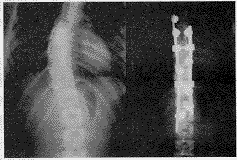

16例脊柱侧凸中,特发性12例,先天性3例,退行性1例。在12例特发性侧凸中,King Ⅲ、Ⅳ型9例,术前侧凸Cobb角平均51.8°,术后Cobb角平均18.4°,矫正率64.5%。KingⅠ、Ⅱ型3例,术前胸段侧凸Cobb角平均92°,术后平均46°,矫正率50%,术前腰段侧凸平均100°,术后平均40°,矫正率60%(图2)。先天性脊柱侧凸术前Cobb角43.3°,术后9.3°,矫正率78.5%。随诊侧凸矫正度无丢失。

图2 特发性脊柱侧凸手术前后X光片